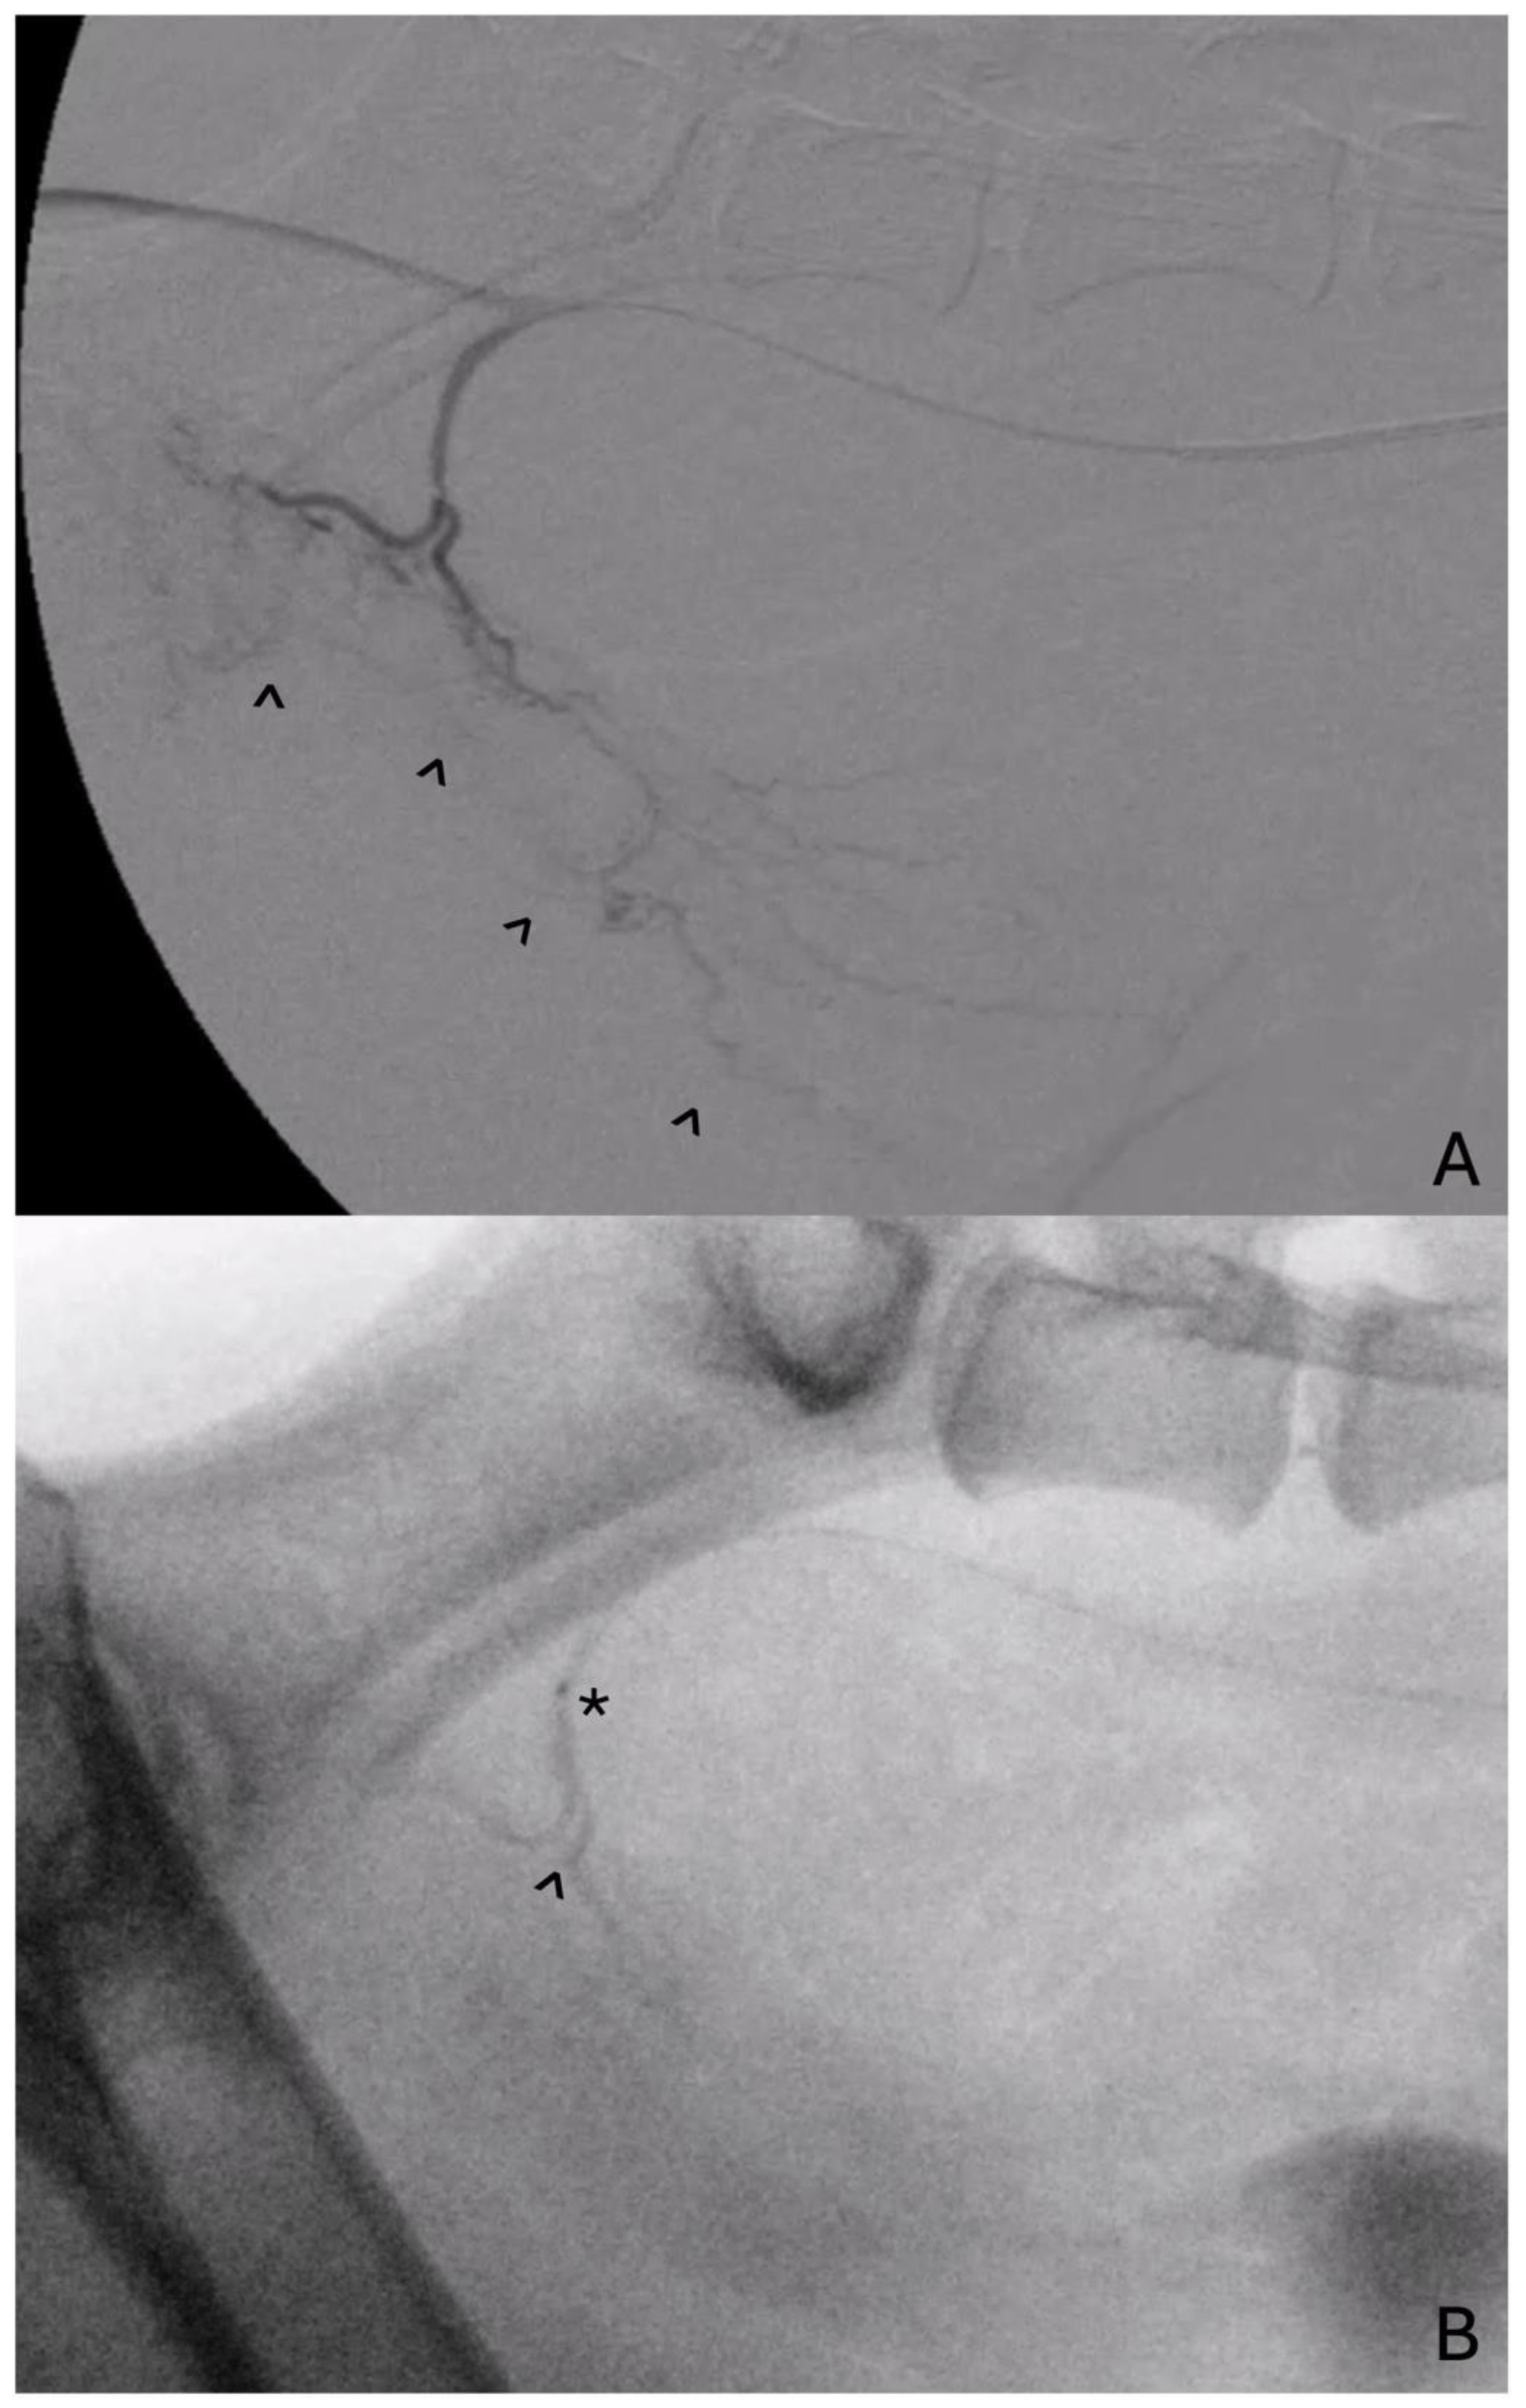

4.1. Prostate Artery Embolization

- Culp, W.T.N.; Johnson, E.G.; Giuffrida, M.A.; Palm, C.A.; Skorupski, K.A.; Burton, J.H.; Rebhun, R.B.; Willcox, J.L.; Kent, M.S.; Rodriguez, C.O.; et al. Procedural Description and Prospective Evaluation of Short-Term Outcome for the Use of Prostatic Artery Embolization in Dogs with Carcinoma of the Prostate. J. Am. Vet. Med. Assoc. 2021, 259, 1154–1162. [Google Scholar] [CrossRef] [PubMed]

- Sun, F.; Sánchez, F.M.; Crisóstomo, V.; Díaz-Güemes, I.; López-Sánchez, C.; Usón, J.; Maynar, M. Transarterial Prostatic Embolization: Initial Experience in a Canine Model. Am. J. Roentgenol. 2011, 197, 495–501. [Google Scholar] [CrossRef] [PubMed]

- Pellerin, O.; Déan, C.; Reb, P.; Chaix, C.; Floch, F.; Tierny, D.; Sapoval, M. Prostate Artery Chemoembolization in Prostate Cancer: A Proof of Concept Study in Spontaneous Prostate Cancer in a Canine Model. Diagn. Interv. Imaging 2021, 102, 709–715. [Google Scholar] [CrossRef] [PubMed]

- Mouli, S.K.; Raiter, S.; Harris, K.; Mylarapu, A.; Burks, M.; Li, W.; Gordon, A.C.; Khan, A.; Matsumoto, M.; Bailey, K.L.; et al. Yttrium-90 Radioembolization to the Prostate Gland: Proof of Concept in a Canine Model and Clinical Translation. J. Vasc. Interv. Radiol. JVIR 2021, 32, 1103–1112.e12. [Google Scholar] [CrossRef] [PubMed]